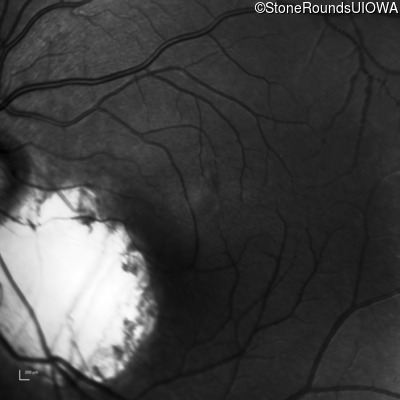

Infrared Fundus Photograph - Right - 20/40 +2

Exemplar